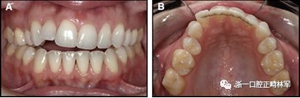

圖4柔軟的螺旋弓絲保持器,下頜右側(cè)尖牙嚴(yán)重的舌側(cè)傾斜以及下頜左側(cè)尖牙的唇側(cè)移位:A,正面視圖; B,咬合面視圖(John Iaculli博士提供)。